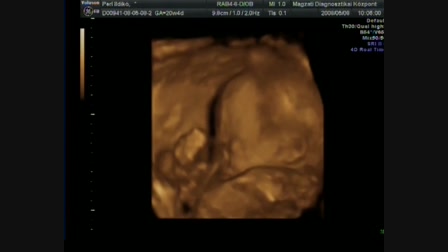

fiam tiszta anyja